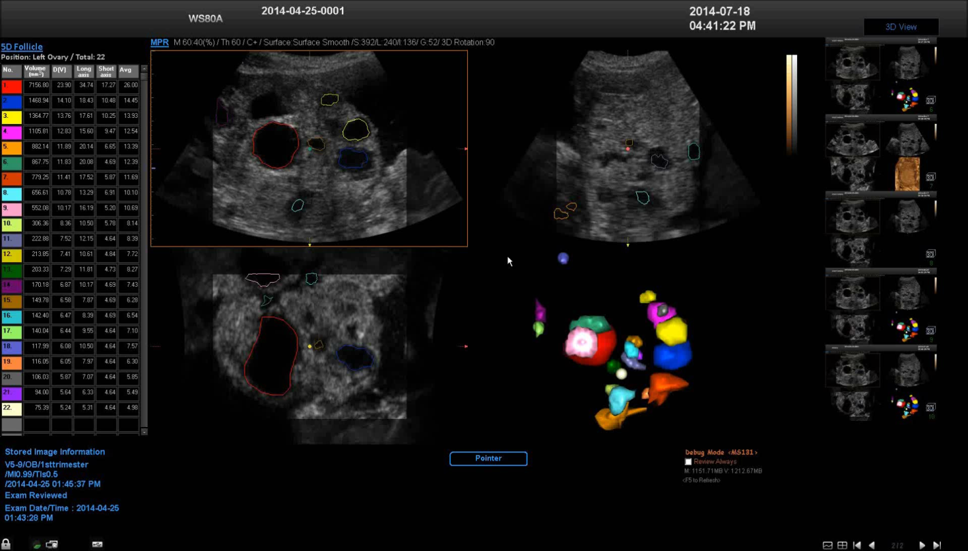

5D Follicle

5D卵泡技术自动识别卵泡,对每个卵泡进行三维重建并用不同颜色呈现出来,同时自动计算并用表格形式列出每个卵泡的多项容积数据。

5D卵泡技术能够有效监测不孕症患者的排卵,通过自动检测和评估卵泡的发育状态提高IVF的成功率。同时能够优化工作流程,并拓展研究者感兴趣领域。